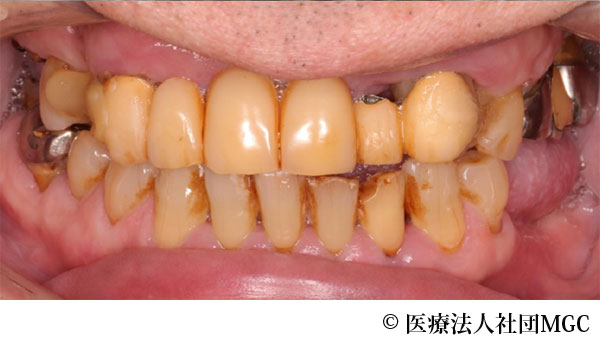

【症例4】上下All-on-4(オールオンフォー)

- 治療前

- 治療後

- 治療名

- 上下All-on-4(オールオンフォー)

- 費用

- 5,888,300円(税込)

- 期間

- 5ヵ月

歯の汚れが気になるのと、奥歯で噛めないとお困りでご来院されました。

ご相談の結果、患者様の生活の質(QOL)を向上させ、しっかり噛め、審美的にも重視した、上下All-on-4(オールオンフォー)を行いました。

機能性、審美性ともに改善し、満足していただけました。